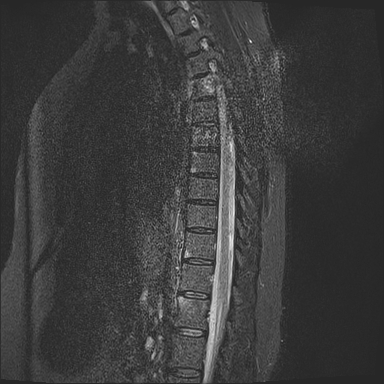

50 yr female was presented with neck and interscapular pain and was referred for MRI covering cervical spine and scapular region. On basis of findings on initial findings, patient was recalled for further MRI imaging.

What are the imaging findings and diagnosis?